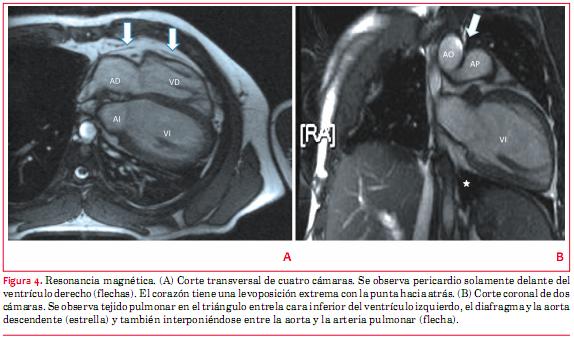

La RM (figura 4) confirmó el diagnóstico con hallazgos característicos del mismo. Desplazamiento global del corazón hacia el hemitórax izquierdo con orientación posterior del ápex. El atrio derecho ocupa una posición retroesternal, el atrio izquierdo “envuelve” la aorta descendente y hay angulación entre la orientación de aurículas y ventrículos. Se observa pericardio solamente por delante del ventrículo derecho, pero no en el resto del corazón. Se observó interposición de una lengüeta de tejido pulmonar entre aorta y arteria pulmonar y también tejido pulmonar en el triángulo entre el diafragma, la cara inferior del corazón y la aorta descendente.

La tomografía computada, y de preferencia la RM, son los métodos de elección para confirmar el diagnóstico. La RM es capaz de establecer en forma directa la ausencia de pericardio. Normalmente el pericardio se visualiza como una fina capa de tejido que separa el tejido adiposo epicárdico de la grasa mediastinal. Su identificación puede ser ardua en personas que tienen poco tejido adiposo epicárdico, lo que puede generar errores. Por este motivo se necesitan criterios diagnósticos adicionales como el ya mencionado desplazamiento característico del corazón hacia el hemitórax izquierdo con la punta hacia atrás y la interposición de tejido pulmonar en lugares en que normalmente el pericardio no lo permite(1,7).